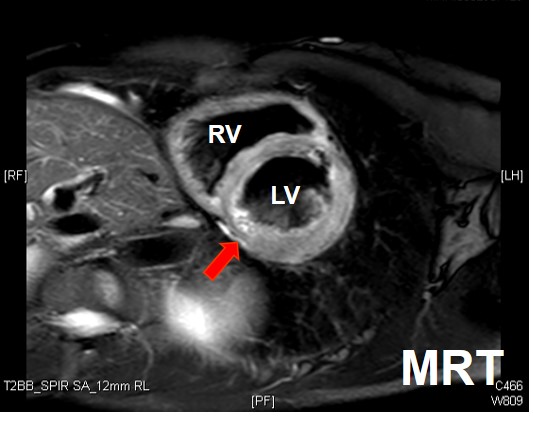

Kardio-MRT

- Kontrastmittelanreicherung

- V.a. Inflammation oder Speicherkrankheit